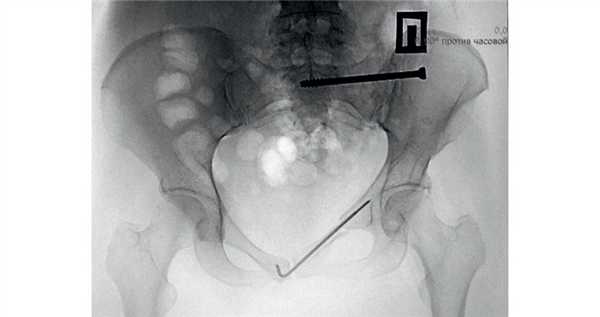

На следующий день после госпитализации для обеспечения ранней активизации пациентке провели минимально инвазивную фиксацию лонной кости спицей с нарезкой и перкутанную фиксацию боковых масс крестца слева канюлированным винтом (рис. 2). Рис. 2. Та же пациентка. Обзорная рентгенограмма после остеосинтеза.

В 1-е сутки после операции пациентка могла садиться и ходить с помощью костылей. Была выписана на 5-е сутки после операции с возможностью самостоятельного обслуживания и передвижения.